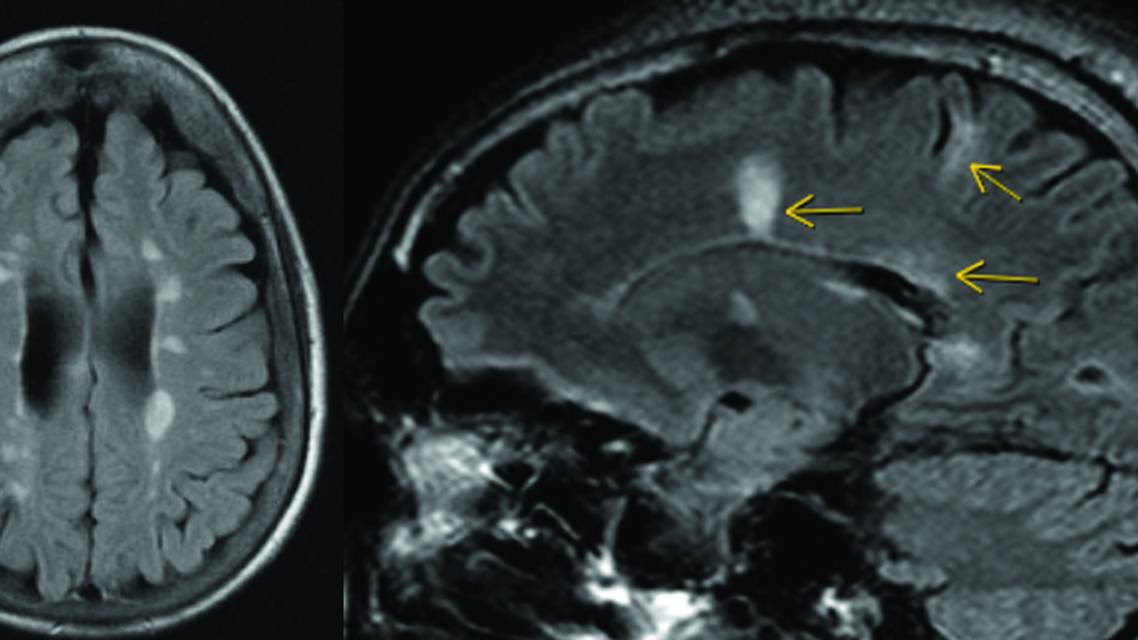

MS lesions have typical features that help differentiate demyelinating lesions from white matter lesions secondary to other causes, including morphology, size, and location. MS lesions tend to be round and ovoid and at least 3 mm in the long axis, often with an asymmetric distribution pattern.11 Classic locations for MS lesions (Figure 1) are juxtacortical/cortical, periventricular, and infratentorial, which serve as 3 of the 5 locations for MS lesions in the McDonald diagnostic criteria. Increased lesion burden, lesion volume, and brain atrophy (whole brain and central) are associated with increased disability as well as worsening of quality of life measures such as cognition, emotional health, and fatigue.12,13

Figure 1. Lesions with a classic multiple sclerosis appearance involving the periventricular and juxtacortical locations on axial (A) and sagittal (B) T2/fluid-attenuated inversion recovery sequences.